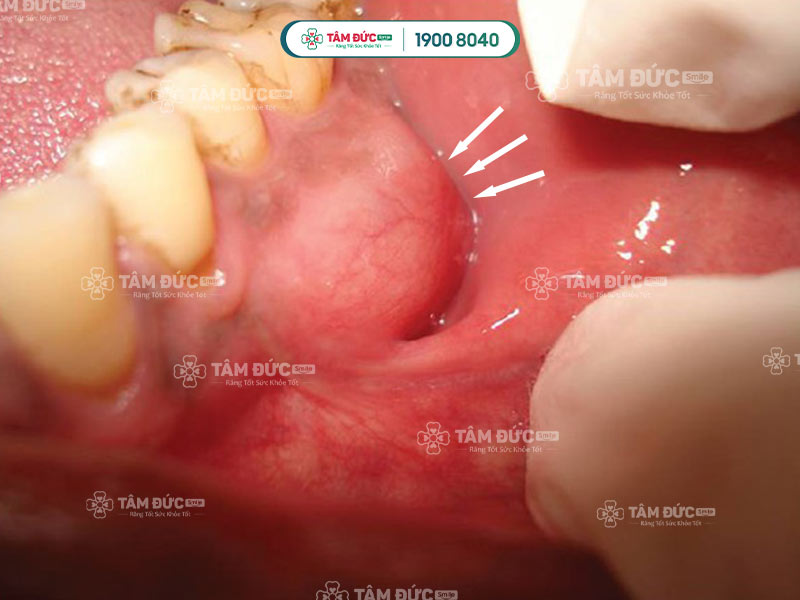

3.2. Viêm lợi có mủ tạo thành khối áp xe chân răng

Áp xe chân răng thường xảy ra khi sâu răng xâm nhập vào tủy mà không được điều trị kịp thời. Đây là tình trạng hình thành ổ mủ tại chân răng, gây đau nhức, sưng hạch cổ, hôi miệng, và sưng mô nướu.